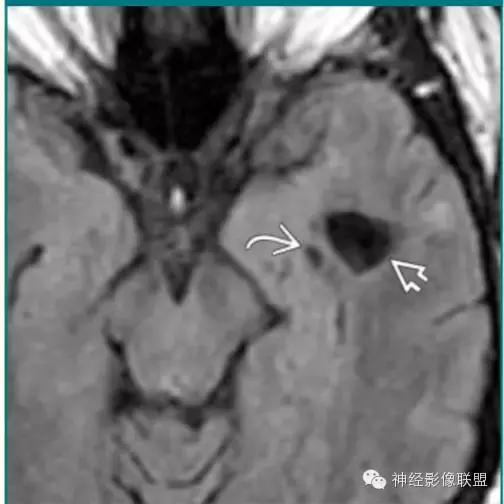

神经脑囊虫病